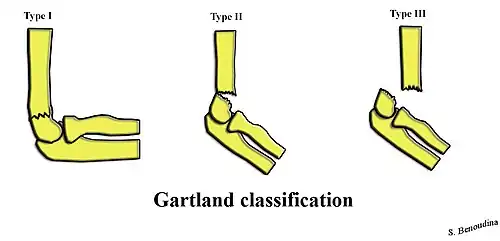

Classification

| Type | Description[3] |

|---|---|

| I | Non-displaced |

| II | Angulated with intact posterior cortex |

| IIA | Angulation |

| IIB | Angulation with rotation |

| III | Complete displacement but have perisosteal (medial/lateral) contact |

| IIIA | Medial periosteal hinge intact. Distal fragment goes posteromedially |

| IIIB | Lateral periosteal hinge intact. Distal fragment goes posterolaterally |

| IV | Periostial disruption with instability in both flexion and extension |

Treatment options for supracondylar humerus fractures vary depending if the bone is displaced (out of position) or not displaced (see classification section above).[1]

Gartland type I

Undisplaced or minimally displaced fractures can be treated by using an above elbow splint in 90 degrees flexion for 3 weeks. Orthopaedic cast and extreme flexion should be avoided to prevent compartment syndrome and vascular compromise. In case the varus of the fracture site is more than 10 degrees when compared to the normal elbow, closed reduction and percutaneous pinning using X-ray image intensifier inside operating theater is recommended. In one study, for those children who was done percutaneous pinning, immobilisation using a posterior splint and an arm sling has earlier resumption of activity when compared to immobilisation using collar and cuff sling. Both methods gives similar pain scores and activity level at two weeks of treatment.[3]

Gartland type II

Gartland Type II fractures requires closed reduction and casting at 90 degrees flexion. Percutaneous pinning is required if more than 90 degrees flexion is required to maintain the reduction. Closed reduction with percutaneous pinning has low complication rates. Closed reduction can be done by applying traction along the long axis of the humerus with elbow in slight flexion. Full extension of the elbow is not recommended because the neurovascular structures can hook around the proximal fragment of the humerus. If the proximal humerus is suspected to have pierced the brachialis muscle, gradual traction over the proximal humerus should be given instead. After that, reduction can be done through hyperflexion of the elbow can be done with the olecranon pushing anteriorly. If the distal fragment is internally rotated, reduction maneuver can be applied with extra stress applied over medial elbow with pronation of the forearm at the same time.[3]

Gartland type III and IV

Gartland III and IV are unstable and prone to neurovascular injury. Therefore, closed or open reduction together with percutaneous pinning within 24 hours is the preferred method of management with low complication rates. Straight arm lateral traction can be a safe method to deal with Gartland Type III fractures. Although Gartland Type III fractures with posteromedial displacement of distal fragment can be reduced with closed reduction and casting, those with posterolateral displacement should preferably be fixed by percutaneous pinning.[3]